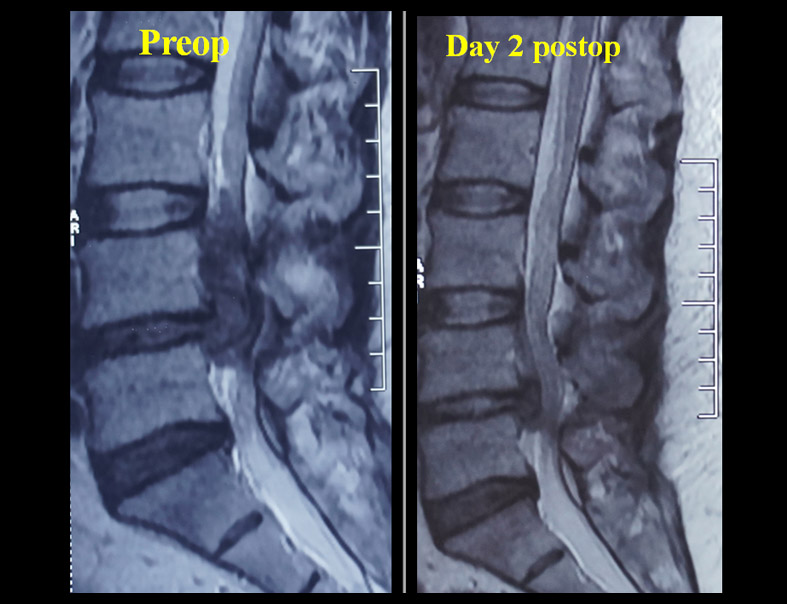

Cauda Equina Syndrome - 45 Yrs/M, with acute onset 5 days old h/o Cauda Equina Syndrome and a large superiorly migrated L4/5 disc as culprit. Among many Endoscopic available options, I still found Destandaus technique a beautiful one in such scenarios.